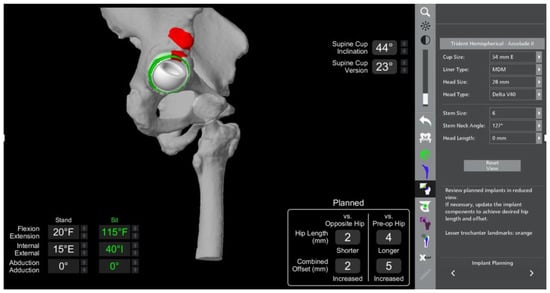

- In this case, the native femoral retroversion (−6 degrees) posed a challenge in avoiding impingement (Figure 7). Upon assessing VROM, bone-on-bone and implant-on-implant impingement in deep flexion were noted (Figure 8). Using the robotic software, the planned femoral version was corrected to +16 in the femoral broach (Figure 9a,b).

- VROM was performed again, and impingement in flexion was eliminated (Figure 10). In extension, upon subtracting the femur, it became apparent that there was a small area of impingement secondary to an anterior osteophyte which was planned to be removed after cup insertion during the operation (Figure 11a,b).

- The robotic software also enables preoperative and intraoperative visualisation of the anticipated postoperative X-rays accounting for any changes to the plan. In addition, the software allows for calculation of changes to the leg length offset compared to the preoperative and contralateral hips. In this case, the leg length was 1 mm longer compared to the opposite hip, and the combined offset was 6 mm increased compared to that preoperatively (Figure 12a,b).